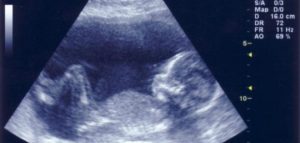

طريقة للتعرف على جنس الجنين دون أشعة!

يرغب كل الآباء والأمهات في معرفة جنس الجنين فور علمهم بخبر الحمل، وأول ما يشغلهم هل سيكون المولود القادم صبيا … Continue reading طريقة للتعرف على جنس الجنين دون أشعة!